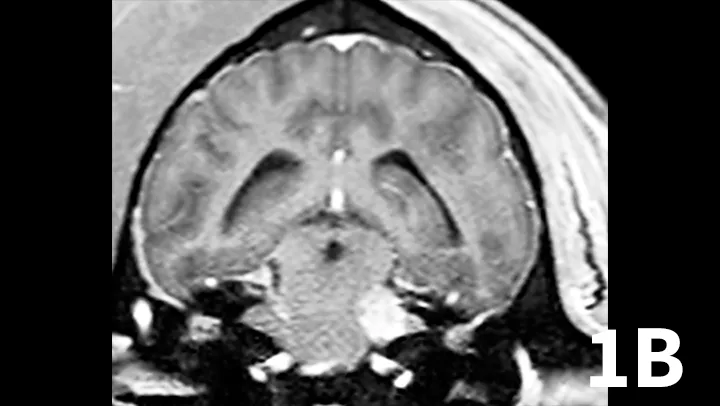

Nerve sheath tumors (NSTs) are perhaps the most common cause of chronic, progressive peripheral cranial nerve disease in older dogs. They arise from Schwann cells or pericytes, are typically slow growing, and are invasive to surrounding nervous system tissue. Metastasis is a rare event associated with NSTs. Whereas they most commonly affect the brachial plexus and lumbosacral plexus, NSTs also can arise within cranial nerves, with the trigeminal nerve most frequently affected. Clinical signs of trigeminal NSTs are ipsilateral to the NST and include unilateral masticatory muscle atrophy, facial hypalgesia, reduced corneal sensation, and Horner syndrome.1 Magnetic resonance imaging (MRI) is the modality of choice for identifying lesions. On MRI, NSTs are mass-like, tubular structures that are contiguous with a nerve (Figure 1).2 Lesions are often hyperintense (bright) on T2-weighted images (T2WIs), indicating high water content from edema, neoplastic cells, or inflammation, and strongly contrast enhance on T1-weighted images (T1WIs) following the delivery of gadolinium, suggesting a blood–nerve barrier breakdown or neoangiogenesis.

Transverse T2WI (A) and postcontrast T1WI (B) from a 10-year-old golden retriever with a 6-month history of left masticatory muscle atrophy. Adjacent to the left lateral pons is a mass-like lesion (arrow) confluent with the left trigeminal nerve that is T2-hyperintense and contrast-enhances on T1WI. There is profound atrophy of the left temporalis muscle (arrowheads), which is likewise T2-hyperintense with subtle contrast enhancement on T1WI. These findings are consistent with a nerve sheath tumor of the proximal trigeminal nerve with secondary neurogenic muscle atrophy.